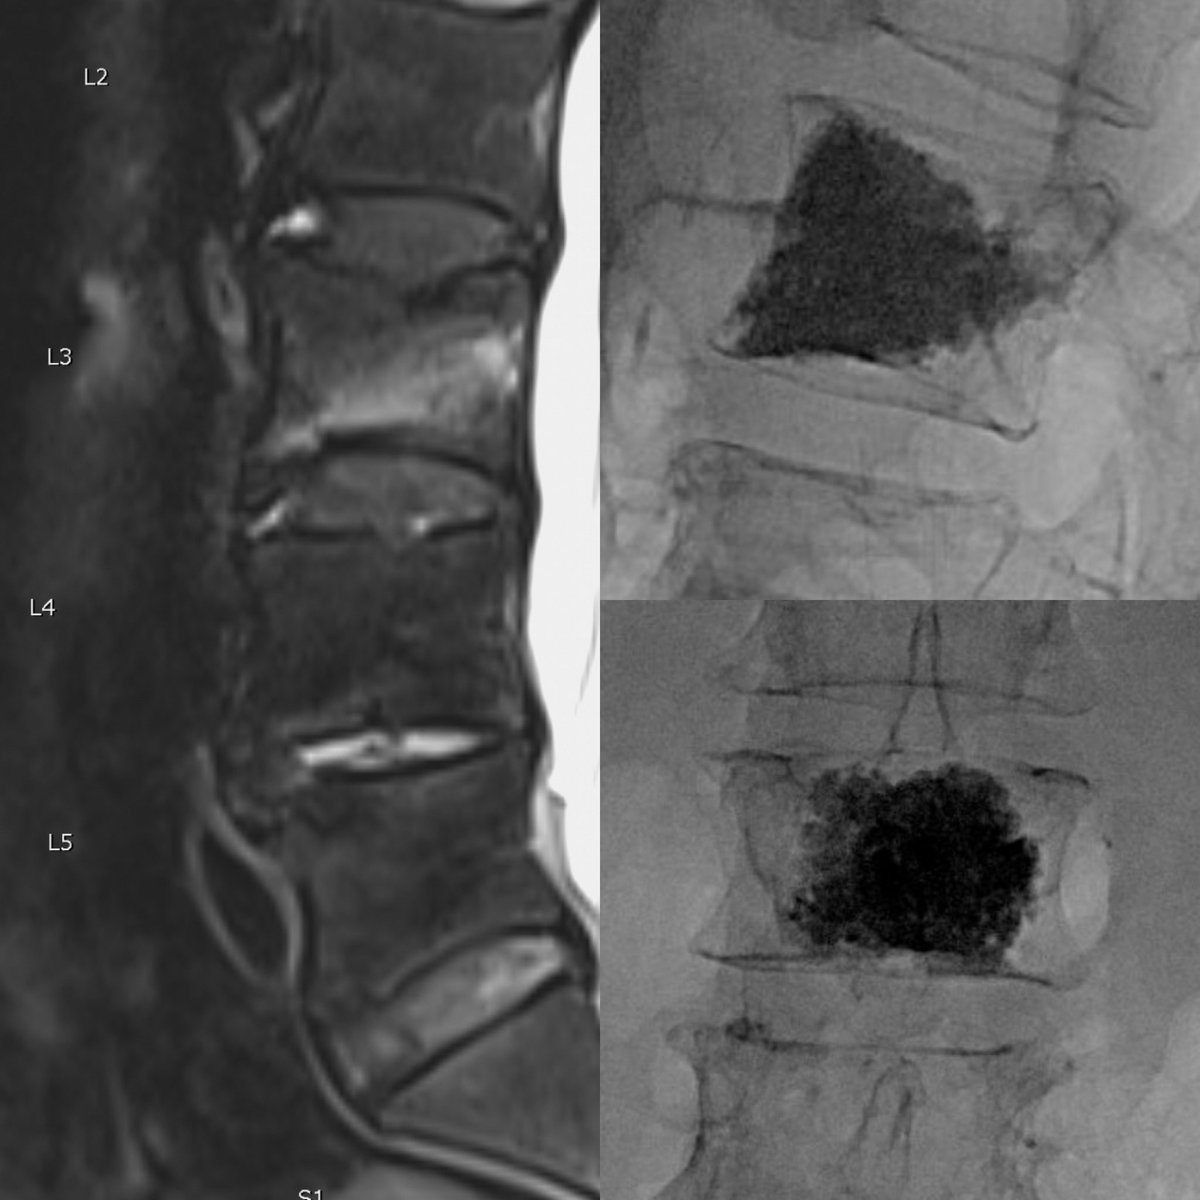

Had a chance to use the Stryker BVN ablation system. Seven minute ablation at 95° C. Easy to use and the case went flawlessly.

Douglas Beall tweet mediaDouglas Beall tweet mediaDouglas Beall tweet mediaDouglas Beall tweet media